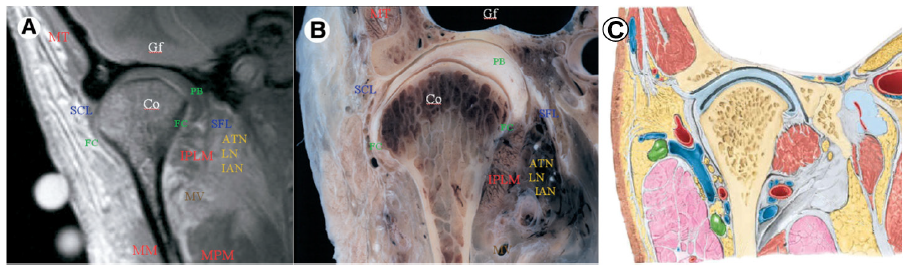

A: RM en T1 corte coronal (MT) Músculotemporal, (MM) Músculo masetero, (IPLM) Vientre inferior del músculo pterigoideo externo, (SFL) Ligamento esfenomandibular, (SCL) Ligamento colateral lateral, (Co) Cóndilo mandibular, (MPM) Músculo pterigoideointerno, [(IAN) Nervio dentario inferior, (LN) Nervio lingual, (ATN) Nervio auriculo temporal, en la RM nose evidencia los nervios solo señala el lugar donde estarían]. Tomado de: Alomar et al., (15). B: Espécimenen coronal. Tomado de: Alomar et al., (15). C: Ilustración en plano coronal. Modificado de: Moore Clinically Oriented Anatomy., (10).

En la figura 6 presentamos cortes coronales a nivel del eje medio - lateral del cóndilo mandibular donde podemos observar estructuras anatómicas de relevancia como: el músculo temporal (TM) evidenciándose por arriba y por fuera del tubérculo articular y hueso temporal respectivamente (banda hipointensa adyacente), la banda posterior del disco (PB), tenuemente isointensa debido a su contenido heterogéneo (contenido vascular y adiposo), también observamos al ligamento capsular interno y al ligamento esfenomandibular (SFL) (isointensos) (figura 6).